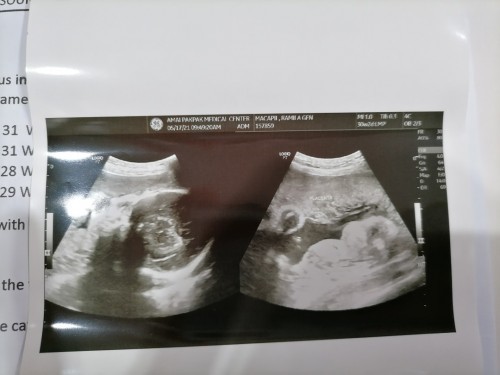

Nag early labor ako nung June 28 nag open cervix ako nang 1cm e nasa 36weeks palang si bb sa tummy ko inagapan agad ako nung 4x dose ng dexa para mag matured ang lungs ni bb kung sakaling gusto na nyang kumawala tas pinainum ako nung pampakapit para di muna lumabas si bb buti nlang naagapan agad, ngayuuun waiting na ulit na mag labor 😊 #1stimemom #pregnancy #TeamJuly